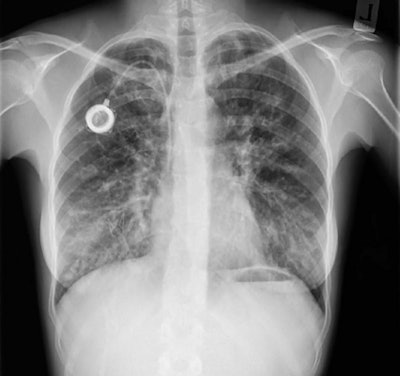

Dynamic chest radiography is a novel real-time digital fluoroscopic imaging system that produces clear, wide field-of-view diagnostic images of the thorax and diaphragm in motion, alongside novel metrics on moving structures within the thoracic cavity.

Dynamic chest radiography images were acquired over 10 seconds with patients in the erect position using a system from Konica Minolta Healthcare. Imaging was performed within 48 hours of pulmonary exacerbation diagnosis and again within 48 hours after the patients' flare-ups had resolved.